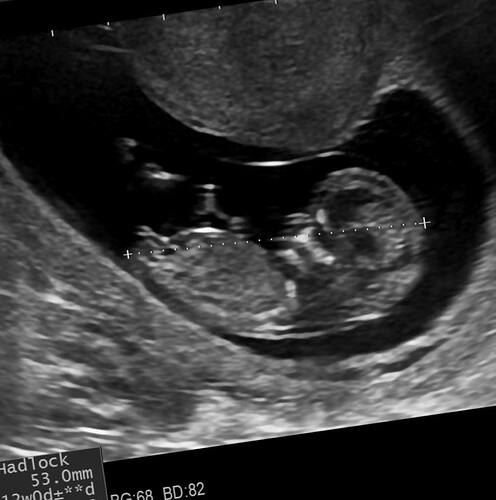

Ay Devlet hastanesindeki doktor kiza benziyor dedi bakalim

Bence erkekkk